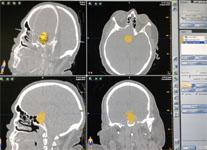

Рис. 3. Маркировка аденомы на виртуальной модели в системе безрамной нейронавигации.